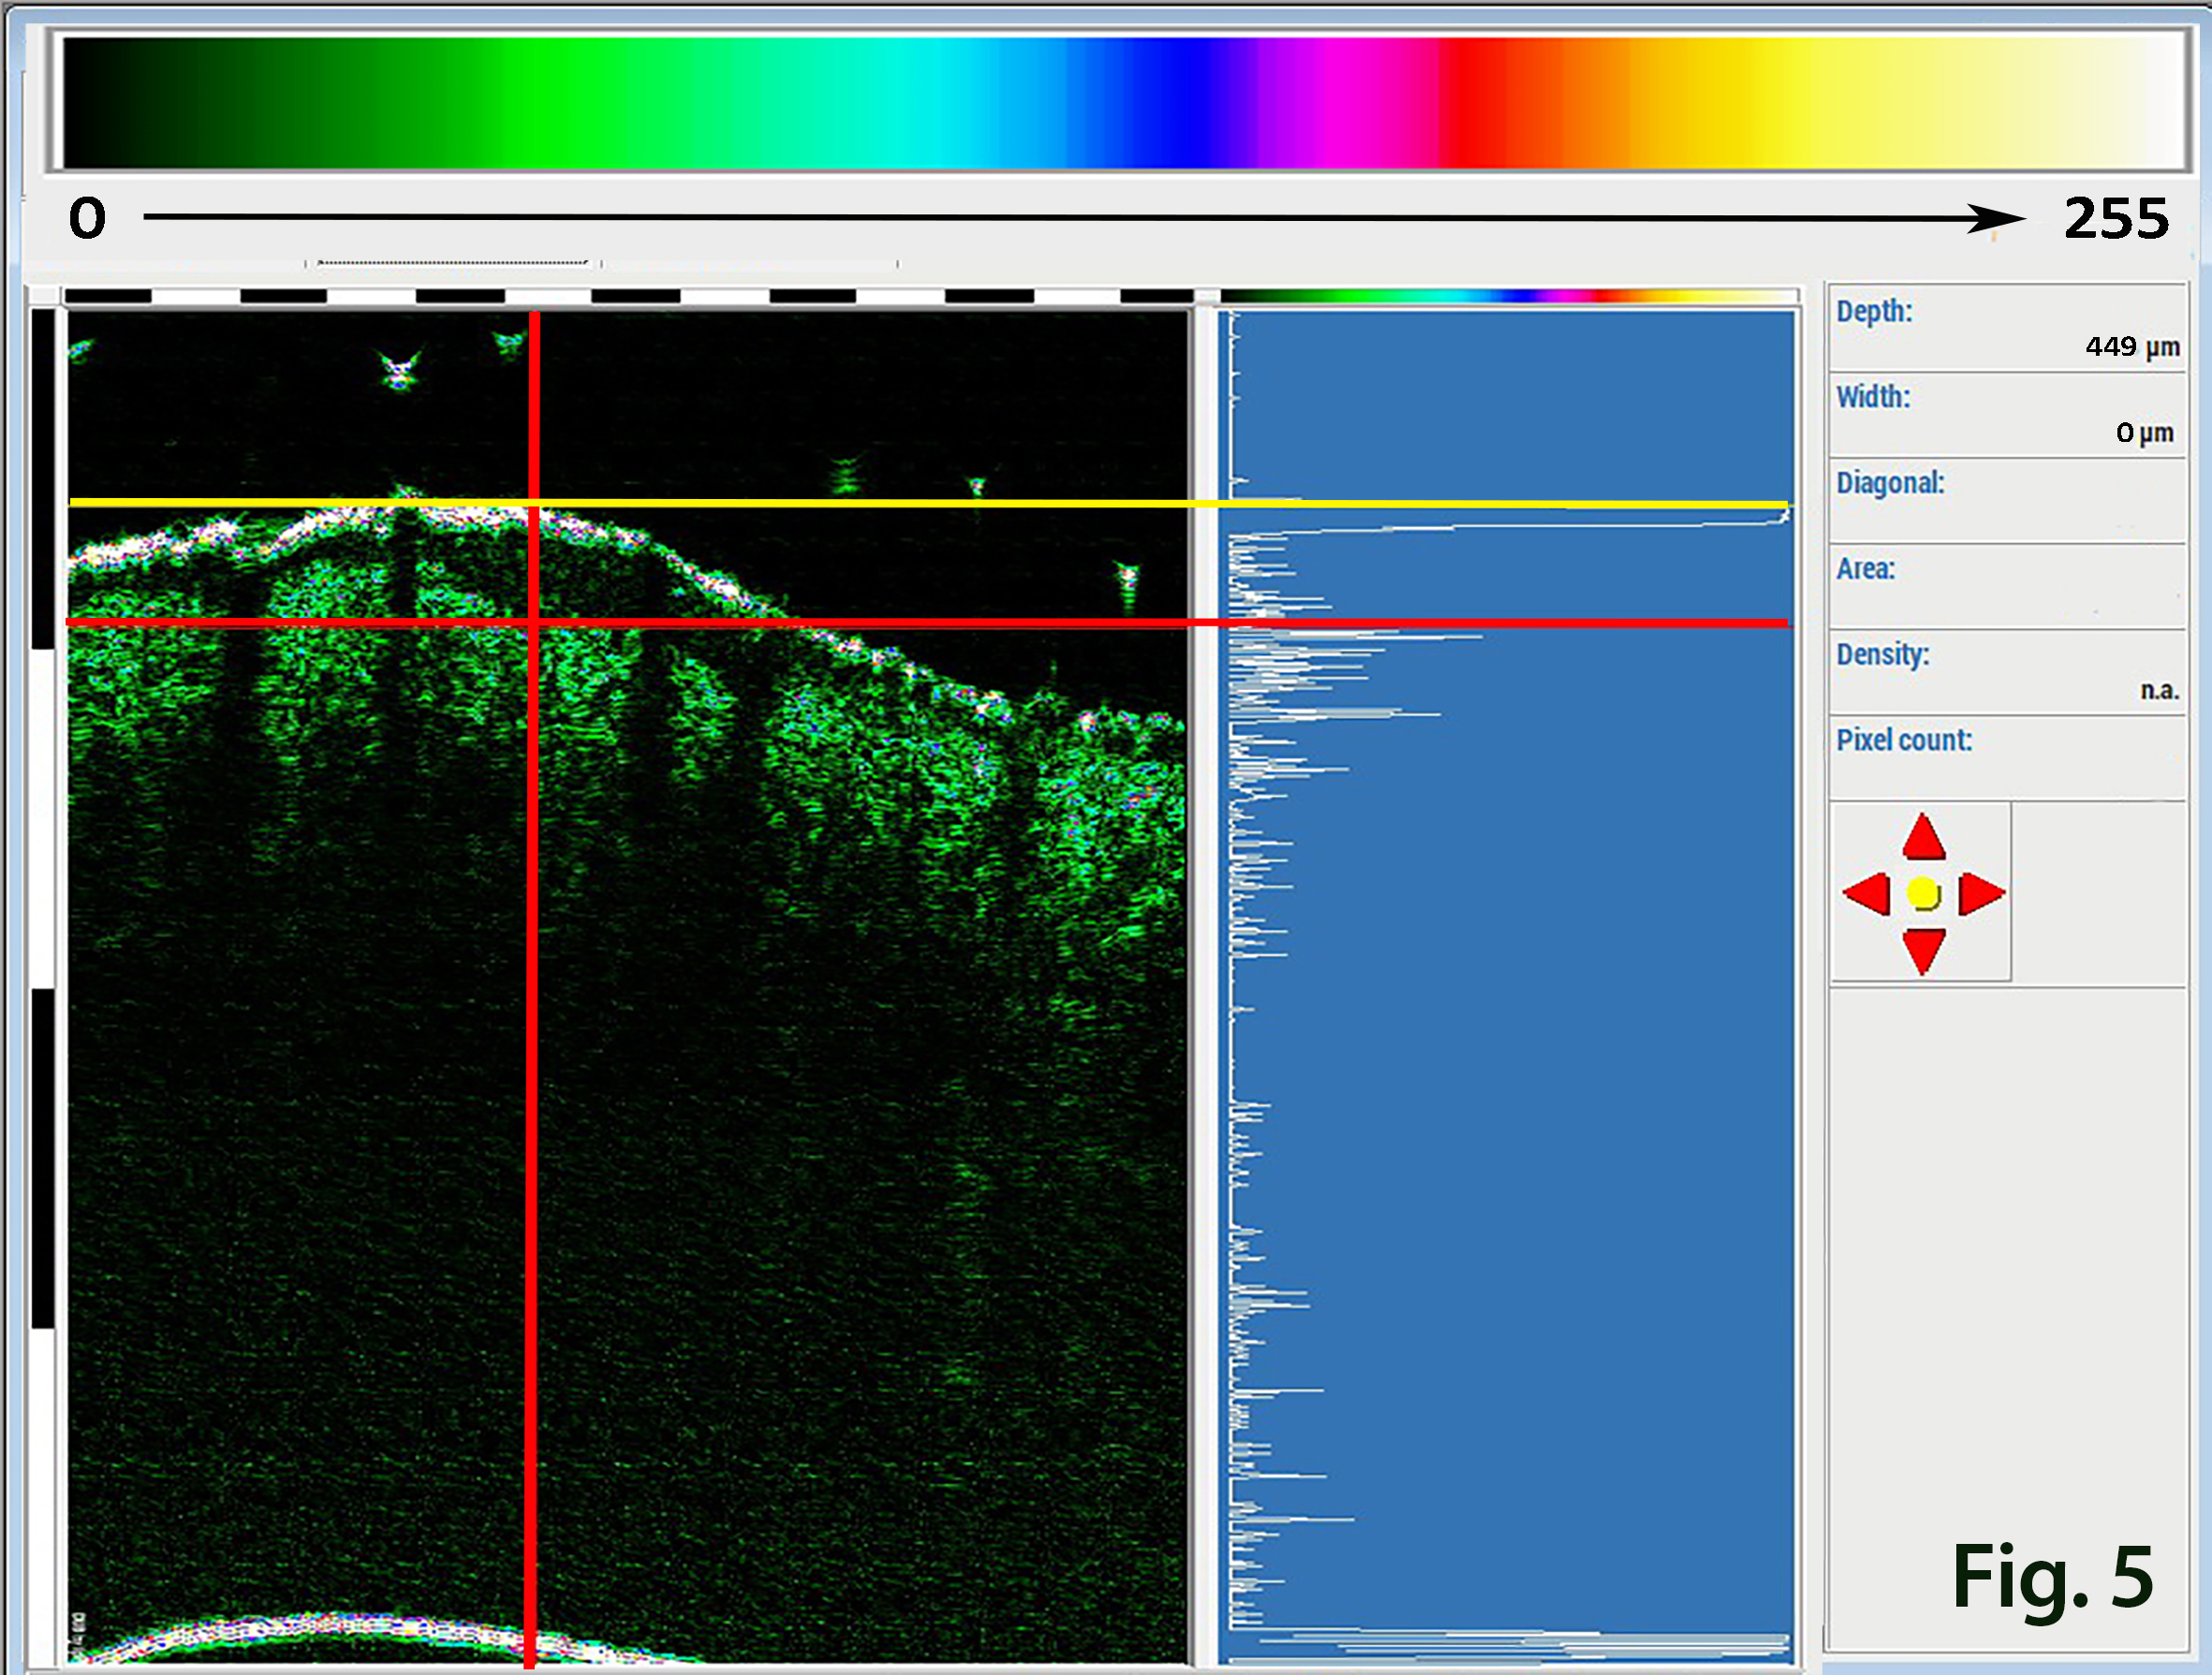

For HFU skin imaging we used a pseudo-color scale (Fig. 5.0) in the range of 0-255; where 0 acoustic density – black, 32 – dark green, 64- light green, 128 - blue, 160 - red 255- white etc. In Fig. 5.0, B and A-scans were combined. The A-Scan corresponds to the vertical red line on the B-Scan.

Figure 5.0. The combination of the B75 MHz B-Scan (left side) and A-Scan (right side). The A scan corresponds to the vertical red line on the B-Scan. The pseudo-colour scale 0-255 is at the top of the image.